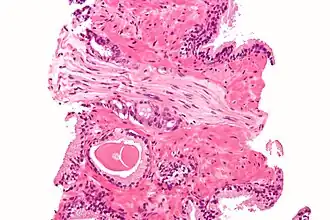

![]() Cross-section of a nerve | |

Each axon is surrounded by a layer of connective tissue called the endoneurium. The axons are bundled together into groups called fascicles, and each fascicle is wrapped in a layer of connective tissue called the perineurium. The entire nerve is wrapped in a layer of connective tissue called the epineurium. Nerve cells (often called neurons) are further classified as either sensory or motor.

Each nerve is covered on the outside by a dense sheath of connective tissue, the epineurium. Beneath this is a layer of fat cells, the perineurium, which forms a complete sleeve around a bundle of axons. Perineurial septa extend into the nerve and subdivide it into several bundles of fibres. Surrounding each such fibre is the endoneurium. This forms an unbroken tube from the surface of the spinal cord to the level where the axon synapses with its muscle fibres, or ends in sensory receptors. The endoneurium consists of an inner sleeve of material called the glycocalyx and an outer delicate meshwork of collagen fibres.[2] Nerves are bundled and often travel along with blood vessels, since the neurons of a nerve have fairly high energy requirements.